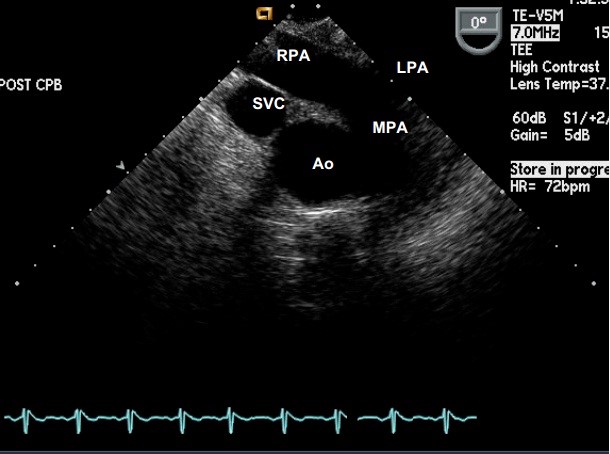

2.2.7. Mặt cắt trục ngang

qua động mạch chủ lên giữa TQ (Mid Esophageal Ascending Aorta short axis view):

* Cách tìm: Từ mặt cắt 4 buồng giữa TQ, rút lui đầu dò dần dần, đồng thời gập

trước (anteflexion) nhẹ đầu dò đến khi thấy được động mạch chủ ngực lên.

* Các cấu trúc khảo sát được: Động mạch chủ lên (Ao), tĩnh mạch chủ trên (SVC),

thân động mạch phổi (MPA), động mạch phổi trái và phải (LPA & RPA)